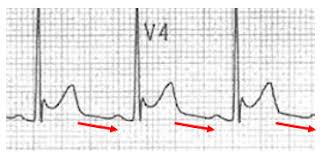

Young patient presenting with acute stitching chest pain What is the most likely explanation ? Vote now in Medshr! The correct answer will be provided after 24 hours in CQ Medshr group Join now for free from here medshr.it/cardioquizzes #cardiotwitter

drahmedmohsen85's tweet image. Young patient presenting with acute stitching chest pain

What is the most likely explanation ?

Vote now in Medshr!

The correct answer will be provided after 24 hours in CQ Medshr group

Join now for free from here

medshr.it/cardioquizzes

#cardiotwitter